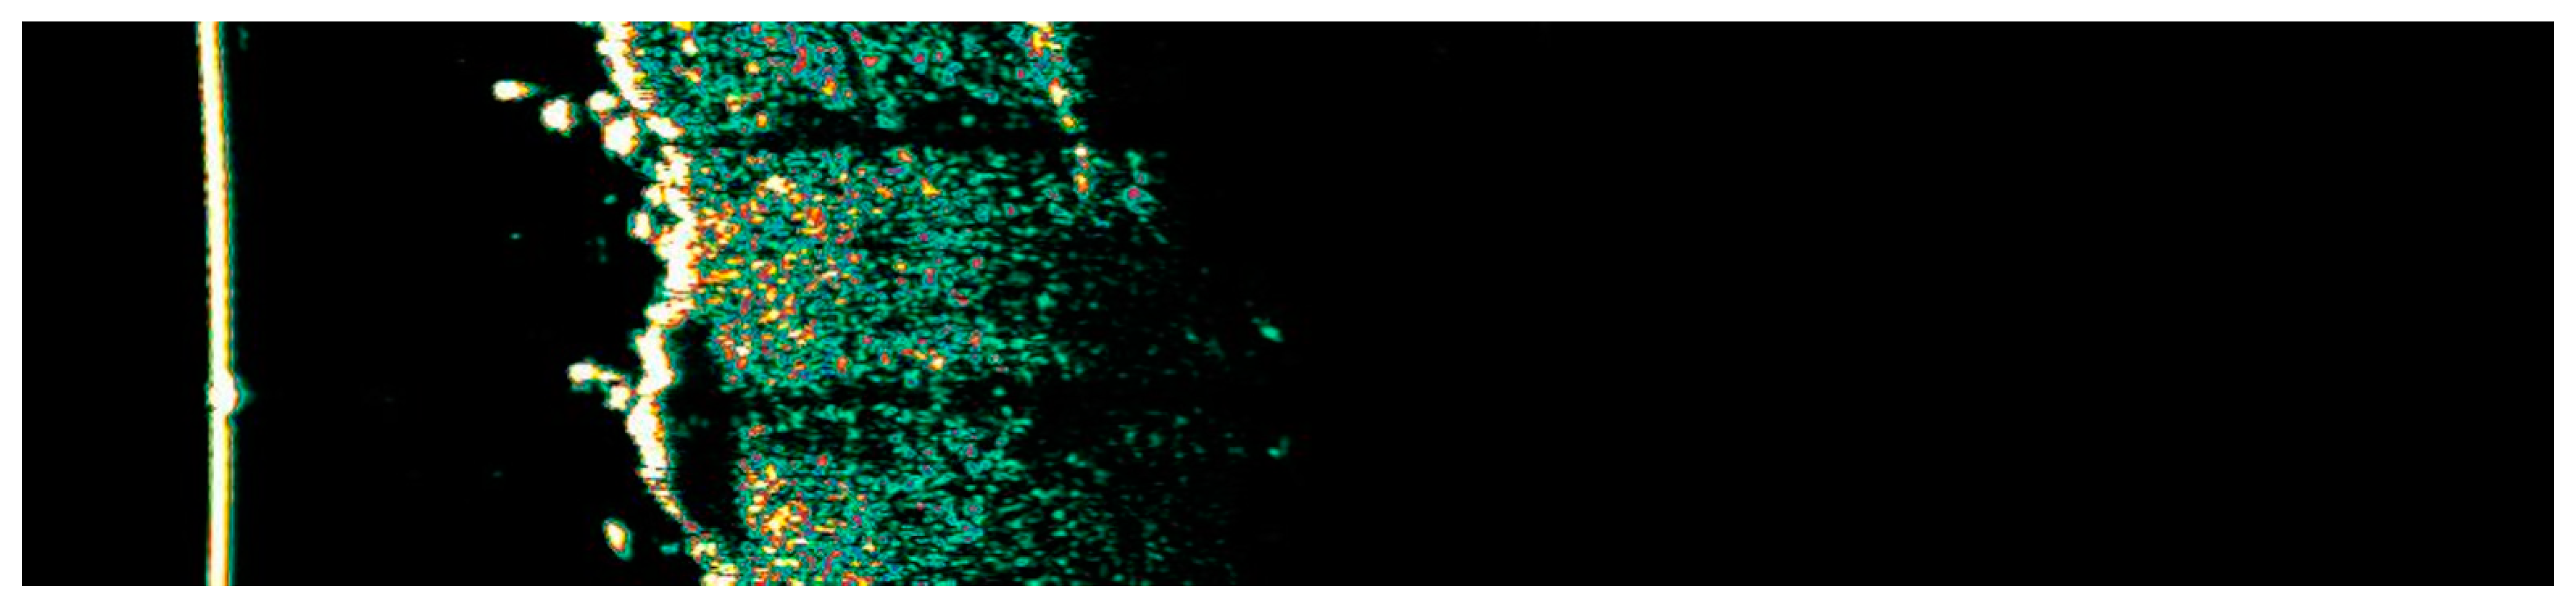

3.1. Clinical and Dermoscopic Involution of HIFU-Treated Basal Cell Carcinoma